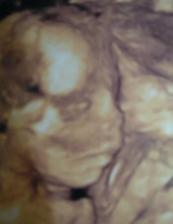

24. srpna 20+2tt - trojitý test, velký a 3D utz, vše OK, děvčátko potvrzeno. Ruce pořád nastřídačku v puse, smála se a kopkala o 106.